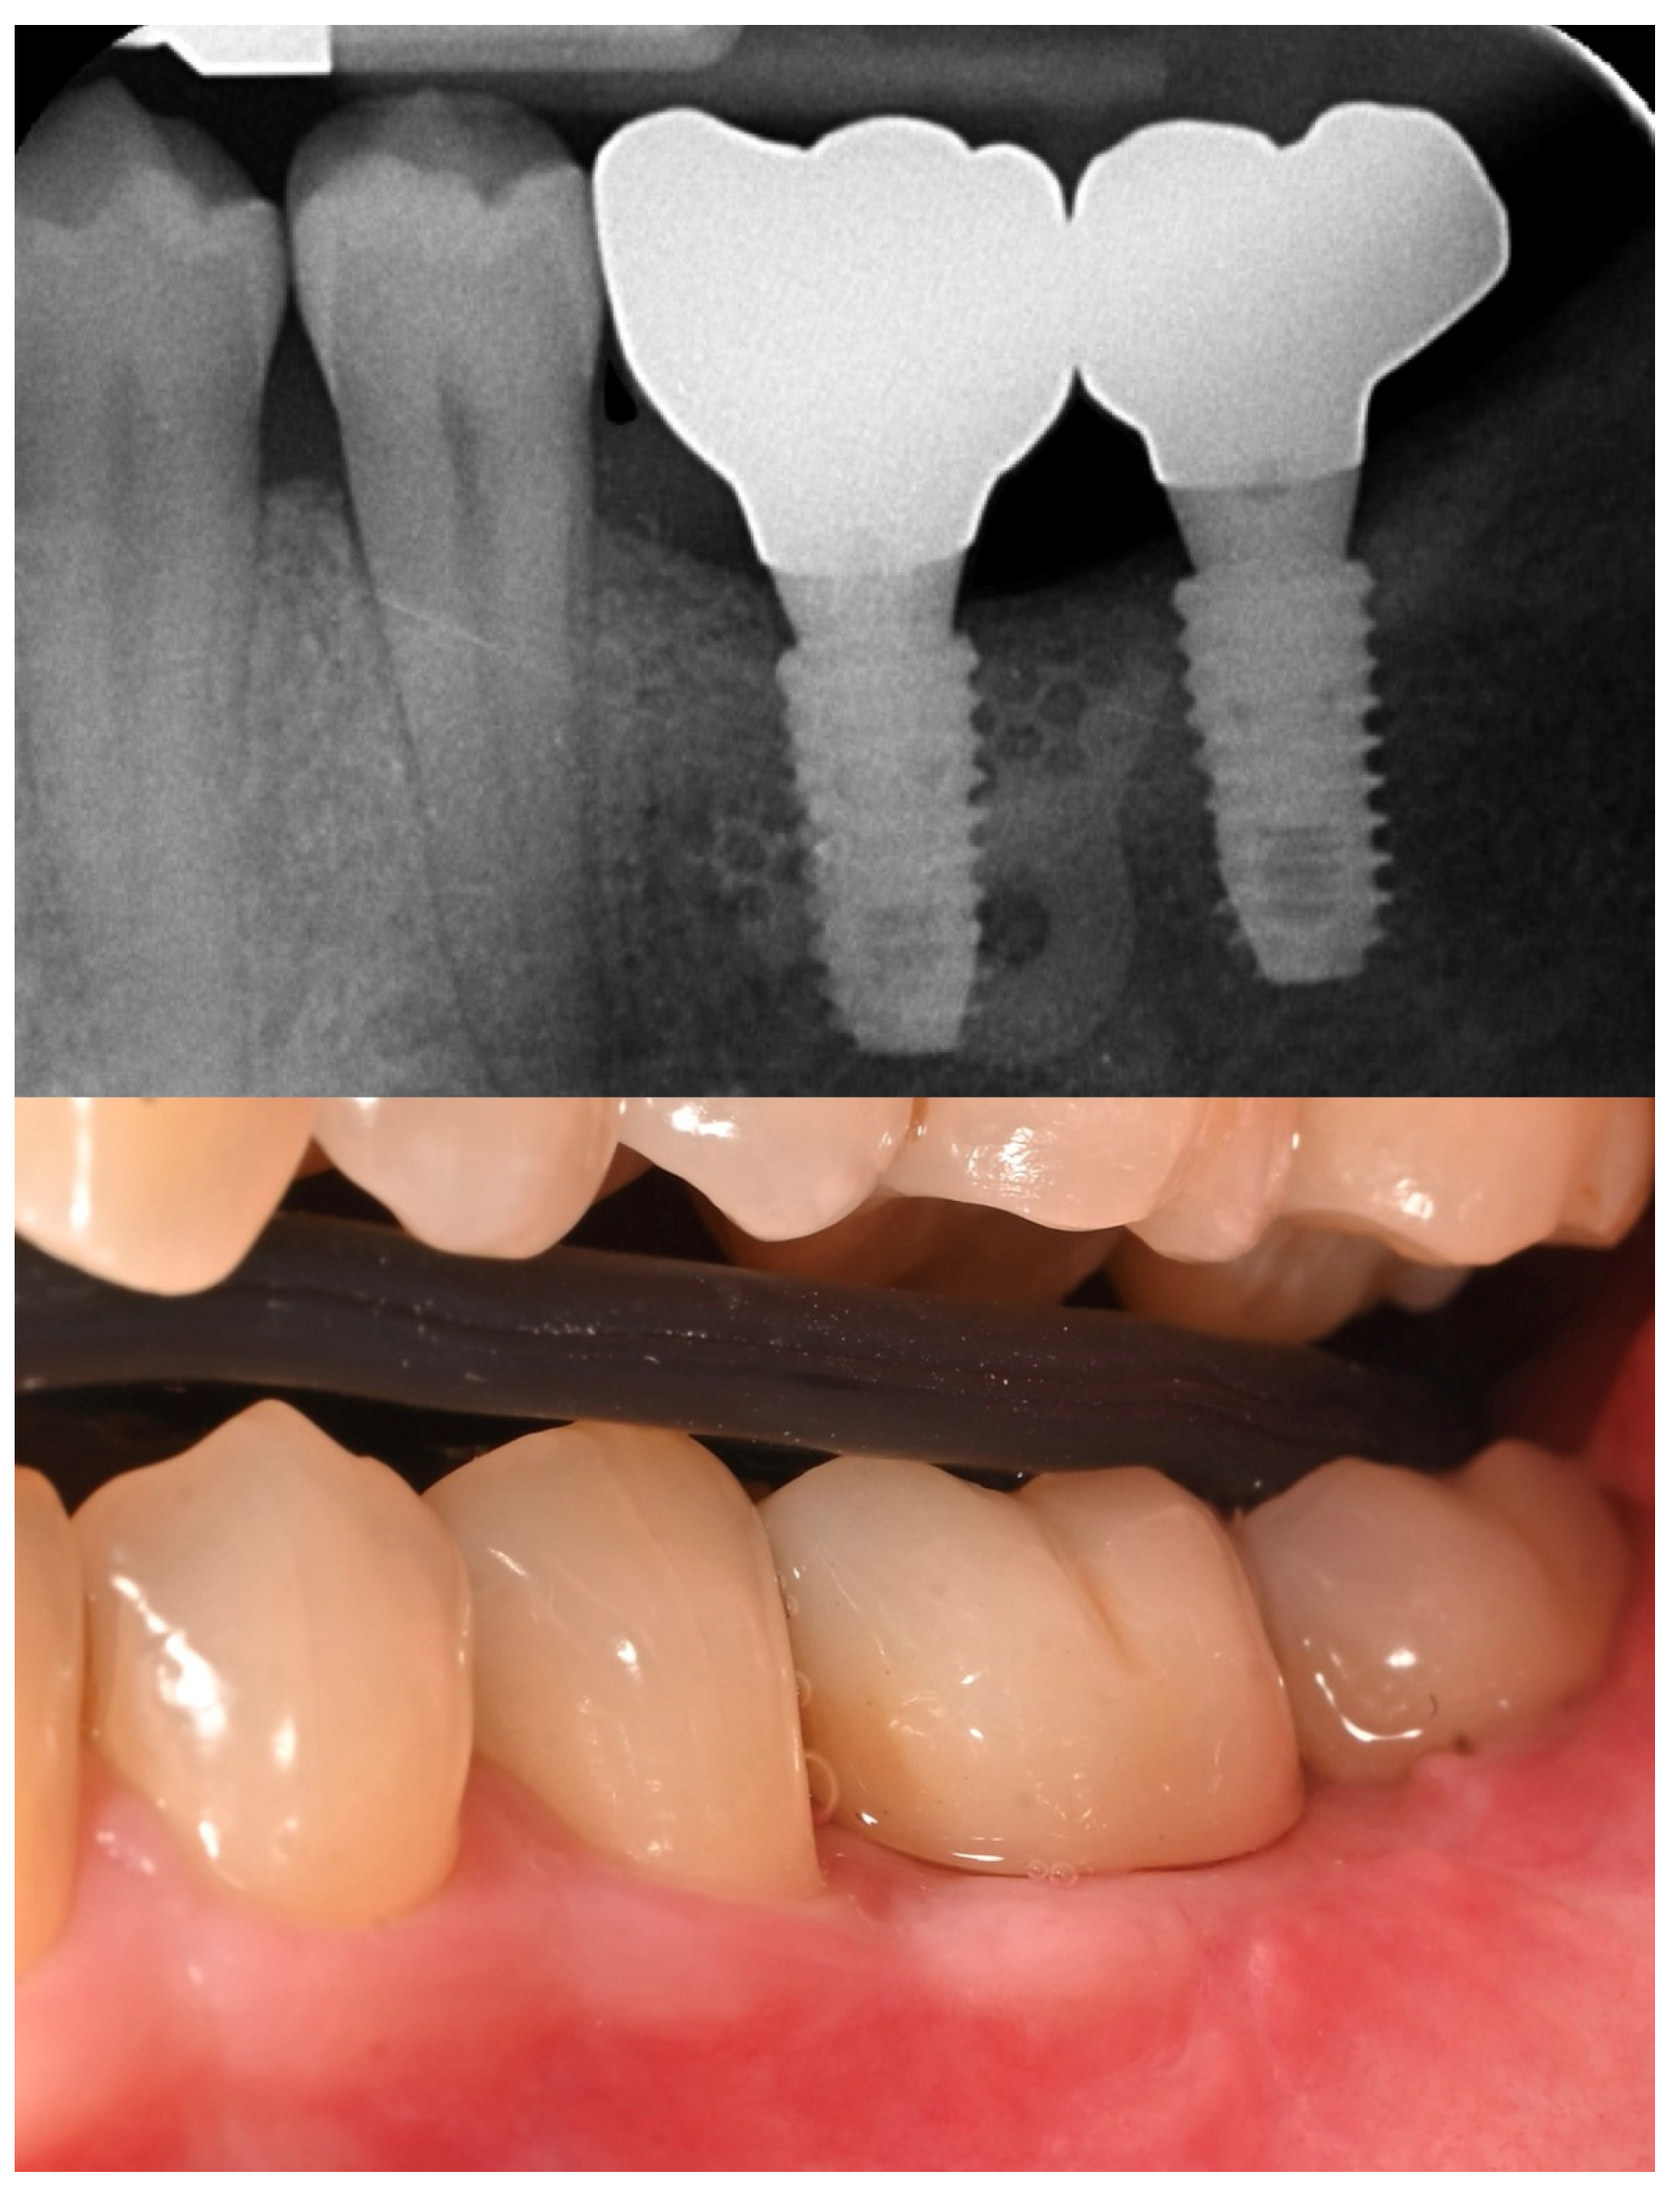

A Second Chance: Managing Late Implant Failure from Peri-Implantitis with Computer-Guided Bone Regeneration—A Clinical Case Report

2. Case Summary